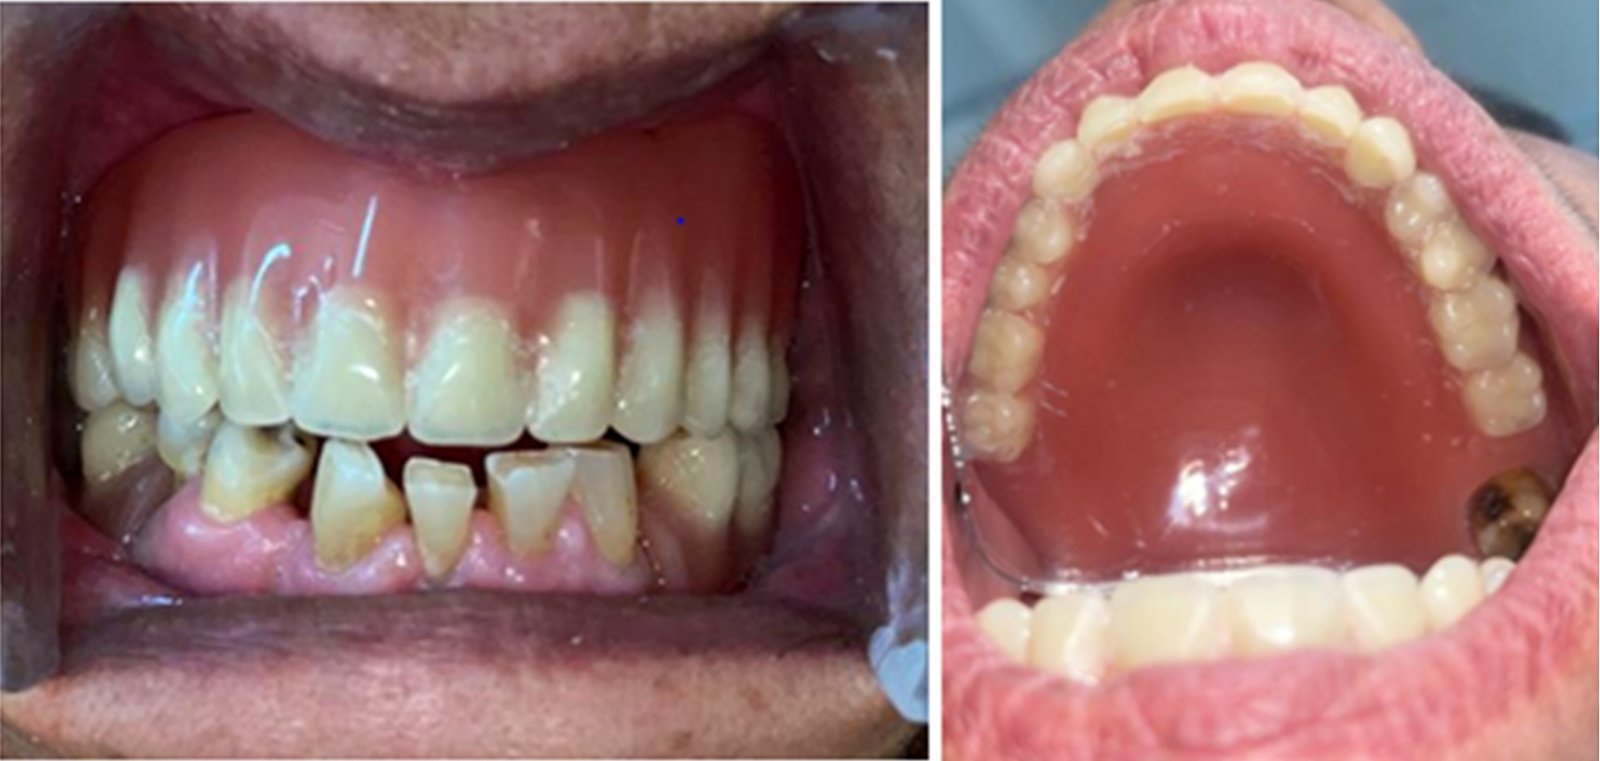

Figure 3 from Cusil denture an innovative approach to preserve the